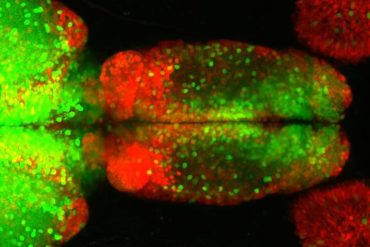

Researchers looked at two components of cells: mitochondria, the cell ‘power houses’ which produce energy for the cell;and the endoplasmic reticulum (ER) which makes proteins and stores calcium for signalling processes in the cell. ER and mitochondria form close associations and these interactions enable a number of important cell functions. However the mechanism by which ER and mitochondria become linked has not, until now, been fully understood.

By studying cells in a dish, the researchers discovered that an ER protein called VAPB binds to a mitochondrial protein called PTPIP51, to form a ‘scaffold’ enabling ER and mitochondria to form close associations. In fact, by increasing the levels of VAPB and PTPIP51, mitochondria and ER re-organised themselves to form tighter bonds.

Many of the cell’s functions that are controlled by ER-mitochondria associations are disrupted in neurodegenerative diseases, so the researchers studied how the strength of this ‘scaffold’ was affected in these diseases. TDP-43 is a protein which is strongly linked to Amyotrophic Lateral Sclerosis (ALS, a form of motor neuron disease) and Fronto-Temporal Dementia (FTD, the second most common form of dementia), but exactly how the protein causes neurodegeneration is not properly understood. The researchers studied how TDP-43 affected mouse cells in a dish. They found that higher levels of TDP-43 resulted in a loosening of the scaffold which reduced ER-mitochondria bonds,affecting some important cellular functions that are linked to ALS and FTD.

Mitochondria and the endoplasmic reticulum (ER) form tight structural associations and these facilitate a number of cellular functions. However, the mechanisms by which regions of the ER become tethered to mitochondria are not properly known. Understanding these mechanisms is not just important for comprehending fundamental physiological processes but also for understanding pathogenic processes in some disease states. In particular, disruption to ER–mitochondria associations is linked to some neurodegenerative diseases. Here we show that the ER-resident protein VAPB interacts with the mitochondrial protein tyrosine phosphatase-interacting protein-51 (PTPIP51) to regulate ER–mitochondria associations. Moreover, we demonstrate that TDP-43, a protein pathologically linked to amyotrophic lateral sclerosis and fronto-temporal dementia perturbs ER–mitochondria interactions and that this is associated with disruption to the VAPB–PTPIP51 interaction and cellular Ca2+ homeostasis. Finally, we show that overexpression of TDP-43 leads to activation of glycogen synthase kinase-3β (GSK-3β) and that GSK-3β regulates the VAPB–PTPIP51 interaction. Our results describe a new pathogenic mechanism for TDP-43.